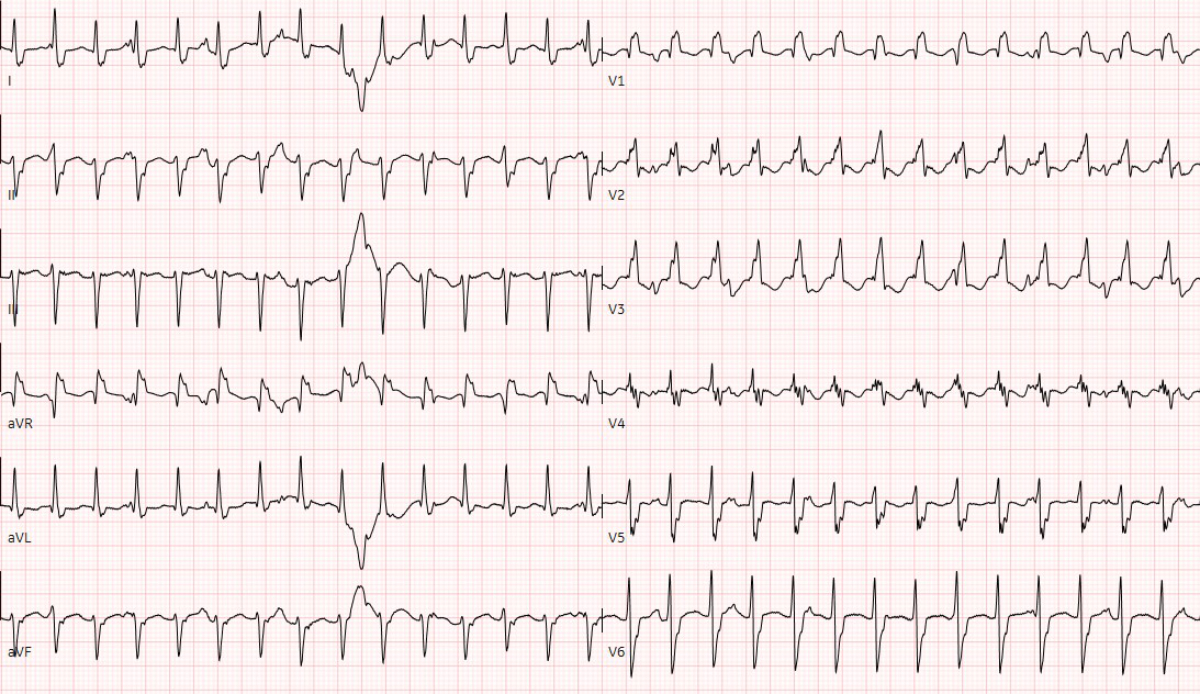

Figure 1 Twelve-lead electrocardiography at admission showed the wide complex ventricular tachycardia with a heart rate of 176 per minute.

Thirteen days after the positive PCR test, he was admitted to our cardiac paediatric intensive care unit in decompensated cardiogenic shock due to a monomorphic ventricular tachycardia (fig. 1) and moderately to severely reduced biventricular cardiac function with a biplane left ventricular ejection fraction of 20%, right ventricular fractional area change of 12%, and fractional shortening of 18% (fig. 2). He was afebrile and the second nasophyrangeal swab for SARS-CoV-2 PCR was still positive after admission. On admission troponin-T was 48 ng/l (reference <14 ng/l), creatinine kinase (CK) 201 U/l (<168 U/l), CK-MB 7.3 µg/l (<6.2 µg/l), and N-terminal-pro-B-type natriuretic peptide (NT-pro-BNP) 10,738 ng/l (<360 ng/l). There were no signs of thrombocytopenia, increased C-reactive protein, and no elevation or decrease of white blood cells or abnormalities in the white blood cells subsets. The clinical status showed no lymphadenopathy, conjunctivitis, mucus membrane changes, rash, or swollen hands and feet. The ventricular tachycardia was recurrent and required electric cardioversion on three occasions within the first 24 hours, in addition to amiodarone therapy. The severely reduced biventricular myocardial function led to progressive pulmonary oedema, pericardial and pleural effusions, and oxygenation failure requiring intubation, high ventilator pressures, inhaled nitric oxide, and bilateral chest drains. A suspected secondary bacterial pneumonia due to the severe clinical (septic) course was treated empirically for 5 days with antibiotics, although cultures remained negative. He was not given additional antiviral therapy due to limited evidence and spontaneous clinical recovery. Progressive low cardiac output with cardiogenic shock and multi-organ dysfunction (acute renal failure RIFLE-I [11], liver dysfunction with coagulopathy) required high-dose inovasodilators. On day 4, creatinine kinase (maximum 2040 U/l) and myoglobin (maximum 669 ng/ml) were at their highest level. The following ECG revealed altered repolarisation (negative T wave up to V6), but no signs of acute infarction. The myocardial function measured by echocardiography improved rapidly, with a left ventricular ejection fraction of 40–50% within 48 hours of admission. After 5 days of inotropic treatment and mechanical ventilation he was transferred to the cardiac ward under treatment with oral diuretics, enalapril, and amiodarone.

Figure 1 Twelve-lead electrocardiography at admission showed the wide complex ventricular tachycardia with a heart rate of 176 per minute.